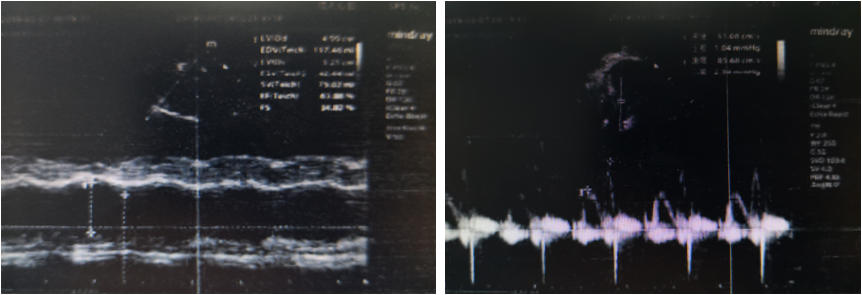

主动脉根部内径24mm 升主动脉内径 28mm 肺动脉主干内径24 mm室间隔厚度8 mm 左心收缩功能EF63% 左心舒张功能E峰51 cm/s FS34 % A峰 85 cm/s左室后壁厚度9 mm 右室流出道 26mm 主动脉最大流速 116 cm/s 肺动脉最大流速 80 cm/s左室舒张末内径 48 mm 左室收缩末内径 30mm 左房 29 mm